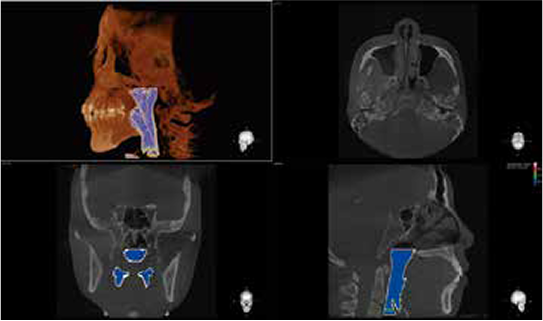

Airway module allows users to easily segment the airway in just a few clicks.